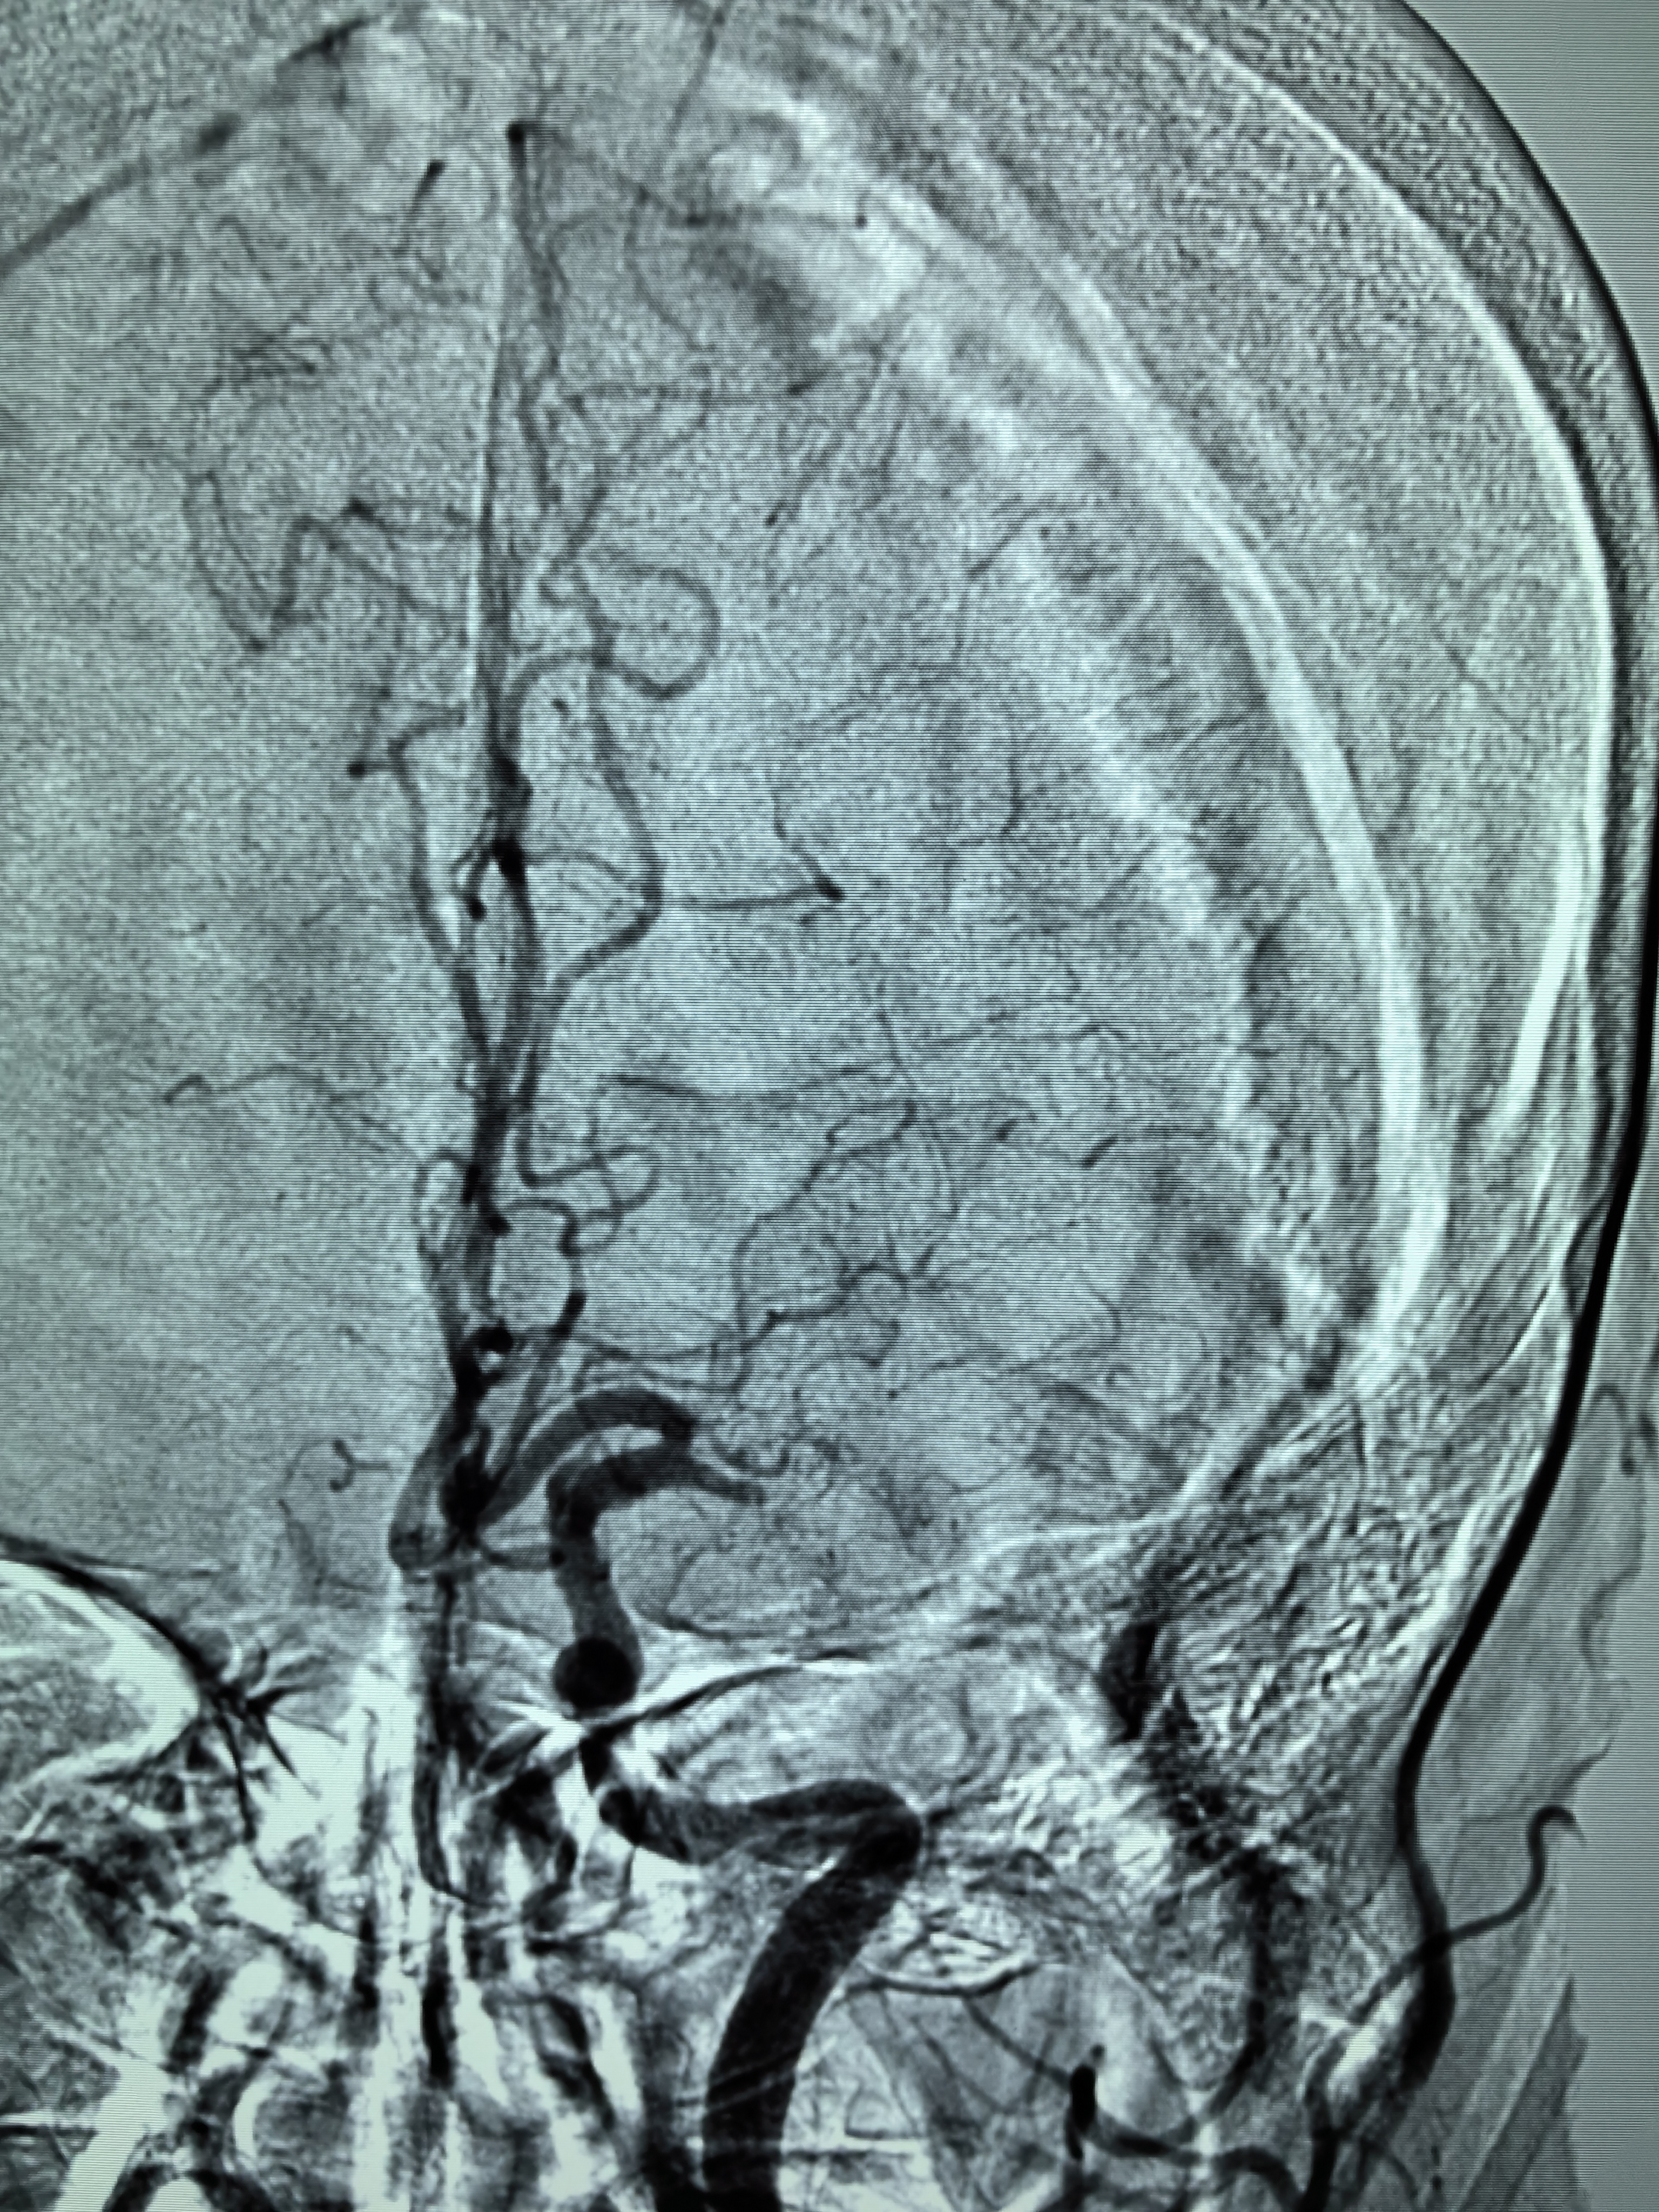

1、本例患者老年女性,系骨科术后次日醒后卒中,经核磁评估提示左侧大脑中动脉闭塞,系责任血管,患者心电图示房颤,考虑心源性栓塞可能性大。

2、本例患者SWIM技术取栓一次后血管再通,颅内血流通畅。